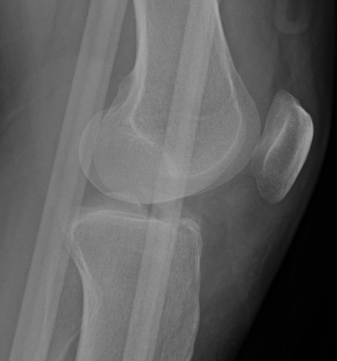

Xray

Xray showing likely Type II with anterior hinging

Type II / III